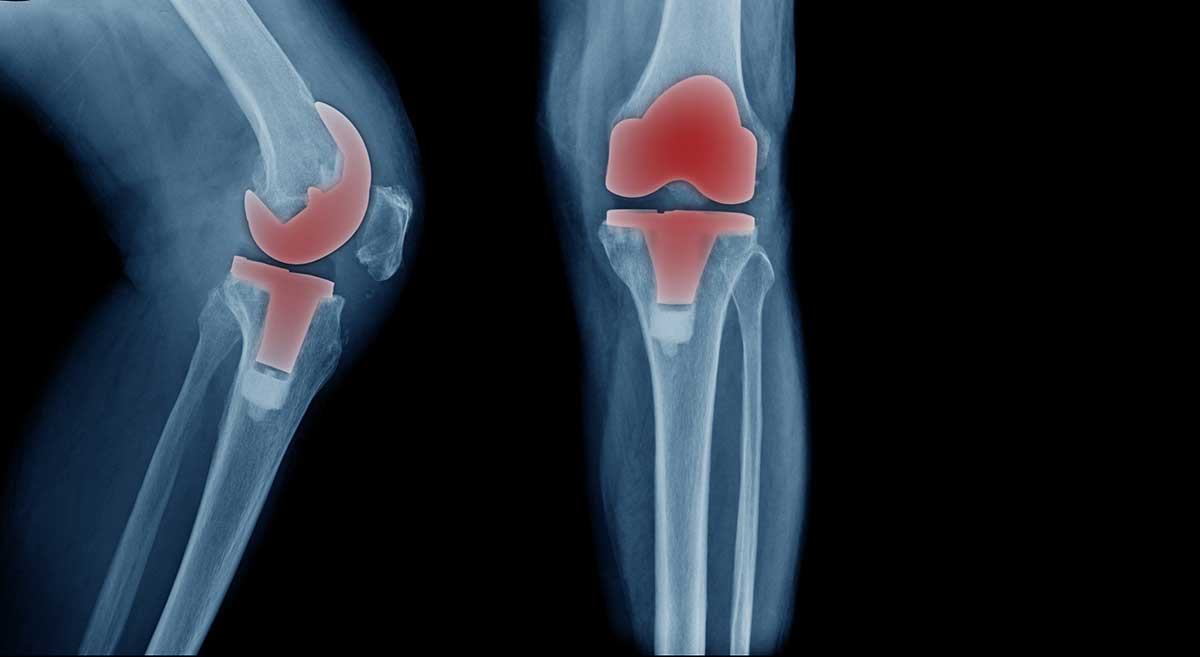

The largest joint in the body, your knee is made of bones, ligaments and cartilage. Injury or arthritis can damage any of these, resulting in pain. When the pain becomes too much, partial or total knee replacement surgery can help.

During the procedure, an orthopaedic surgeon removes all or part of the damaged knee joint. The surgeon then implants a new, artificial joint in its place. Thanks to minimally invasive techniques, the procedure is often done through smaller incisions. This allows many patients to return home the same day and enjoy a faster recovery.